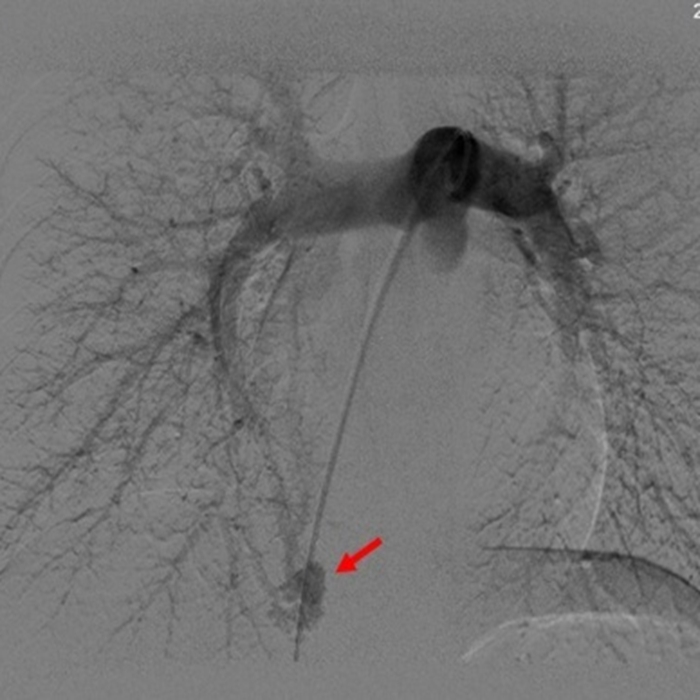

针对患者的情况,闫朝武带领柳昂、齐晨医师,在充分评估病变特征和手术路径的基础上,决定采用同步封堵的策略。术中,团队凭借娴熟的介入技术,通过微创穿刺,精准地将导丝和导管分别送至两处病变位置,并顺利实施封堵。术后即刻复查造影显示,封堵器形态良好、位置稳定,异常分流消失。患者术后恢复良好,头痛症状完全消失。